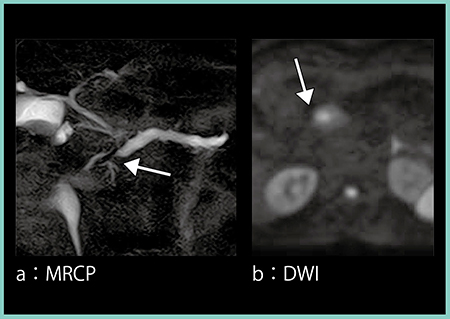

症例1は,80歳代,女性。心窩部痛を主訴に当院を受診し,超音波にて主膵管の拡張と蛇行,および低エコーの腫瘤が認められ(図1↓),膵癌を強く疑い精査となった。CTにて膵体部に造影不良域を認め(図2→),MRCPでは体部主膵管の狭窄と尾側膵管の拡張があり(図3 a←),拡散強調画像(DWI)にて陽性信号(図3 b↓)が認められたことから膵癌と診断し,外科的切除を行った。腫瘍最大径9mm,TMN分類ではT1N0M0,ステージⅠAの比較的早期の膵癌であった。

図3 症例1:早期膵癌のMR画像